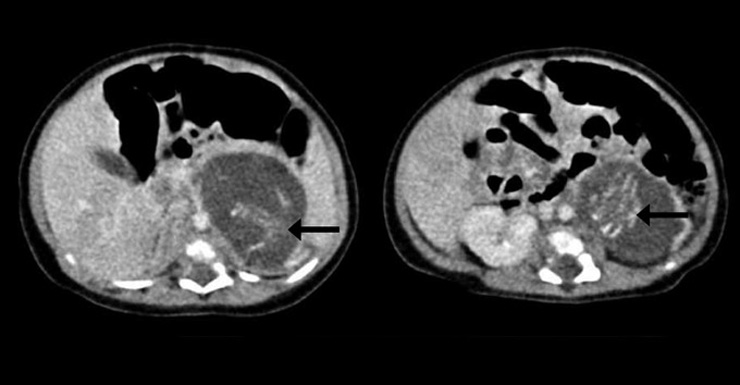

First thought to be a tumour, when doctors cut open the mass they found two tiny little humans complete with arms and legs, bones, brains, and underdeveloped organs.

If these were indeed the baby’s brothers and/or sisters, it would be an example of a very rare condition known as ‘foetus-in-fetu’, which has been reported only 200 times in medical literature, the report in the Hong Kong Medical Journal said.